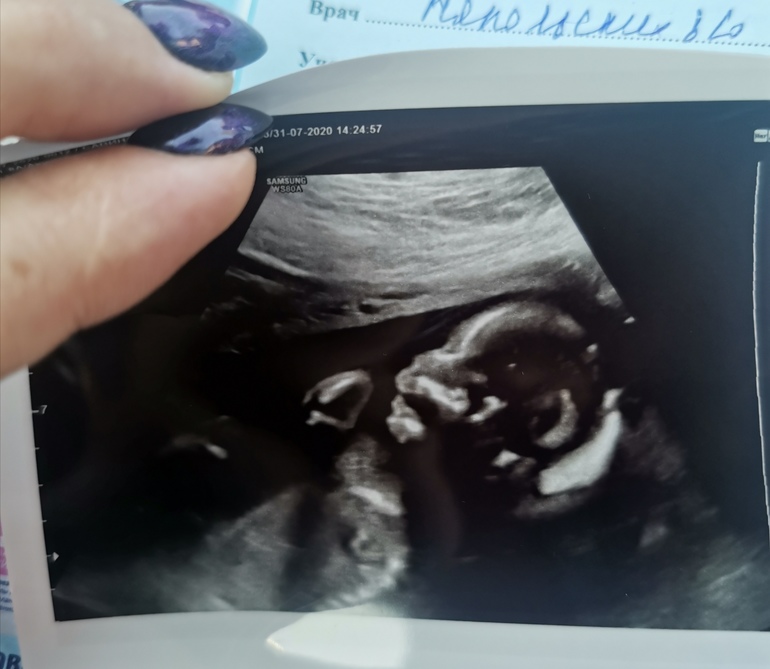

2 скрининг пройден💙

БеременностьСегодня был 2 скрининг. С сыночком все хорошо 🙏🏻 все соответствует сроку, где-то даже обгоняем. Манюнька уже 300 гр.💪🏻💪🏻💪🏻

Коротко о самом скрининге : делала УЗИ у одного из самых знаменитых местных узистов - у Горлова Р. А. Не знаю, почему все его восхваляют(может он действительно божественно определяет патологии), все 40 минут он что-то бубнил под нос. Большую часть молчал. Единственное чётко сказал, что у нас мальчишка 🙋🏼♂️В конце сказал, что все хорошо.

Ну и фото нашей любви 🤘🏻